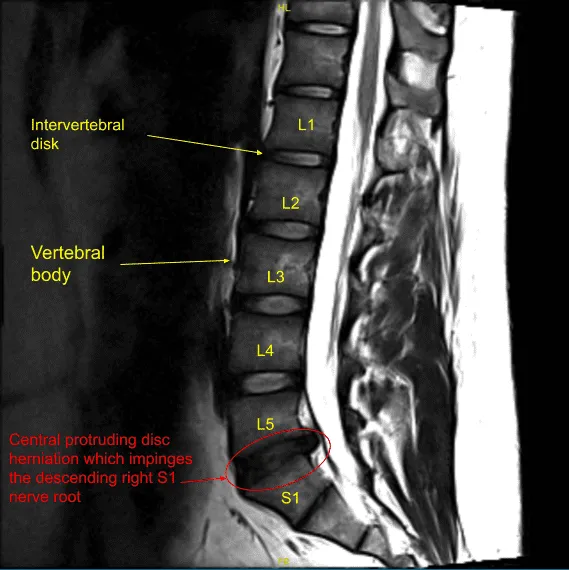

The patient had a radiating pain along the back of the right thigh and leg into the sole of the foot for which they were seeing me as an outpatient. We got an MRI, which showed disc herniation and compression of the right S1 nerve root. We discussed treatment options. The patient tried Medrol-Dosepak, which did not help.